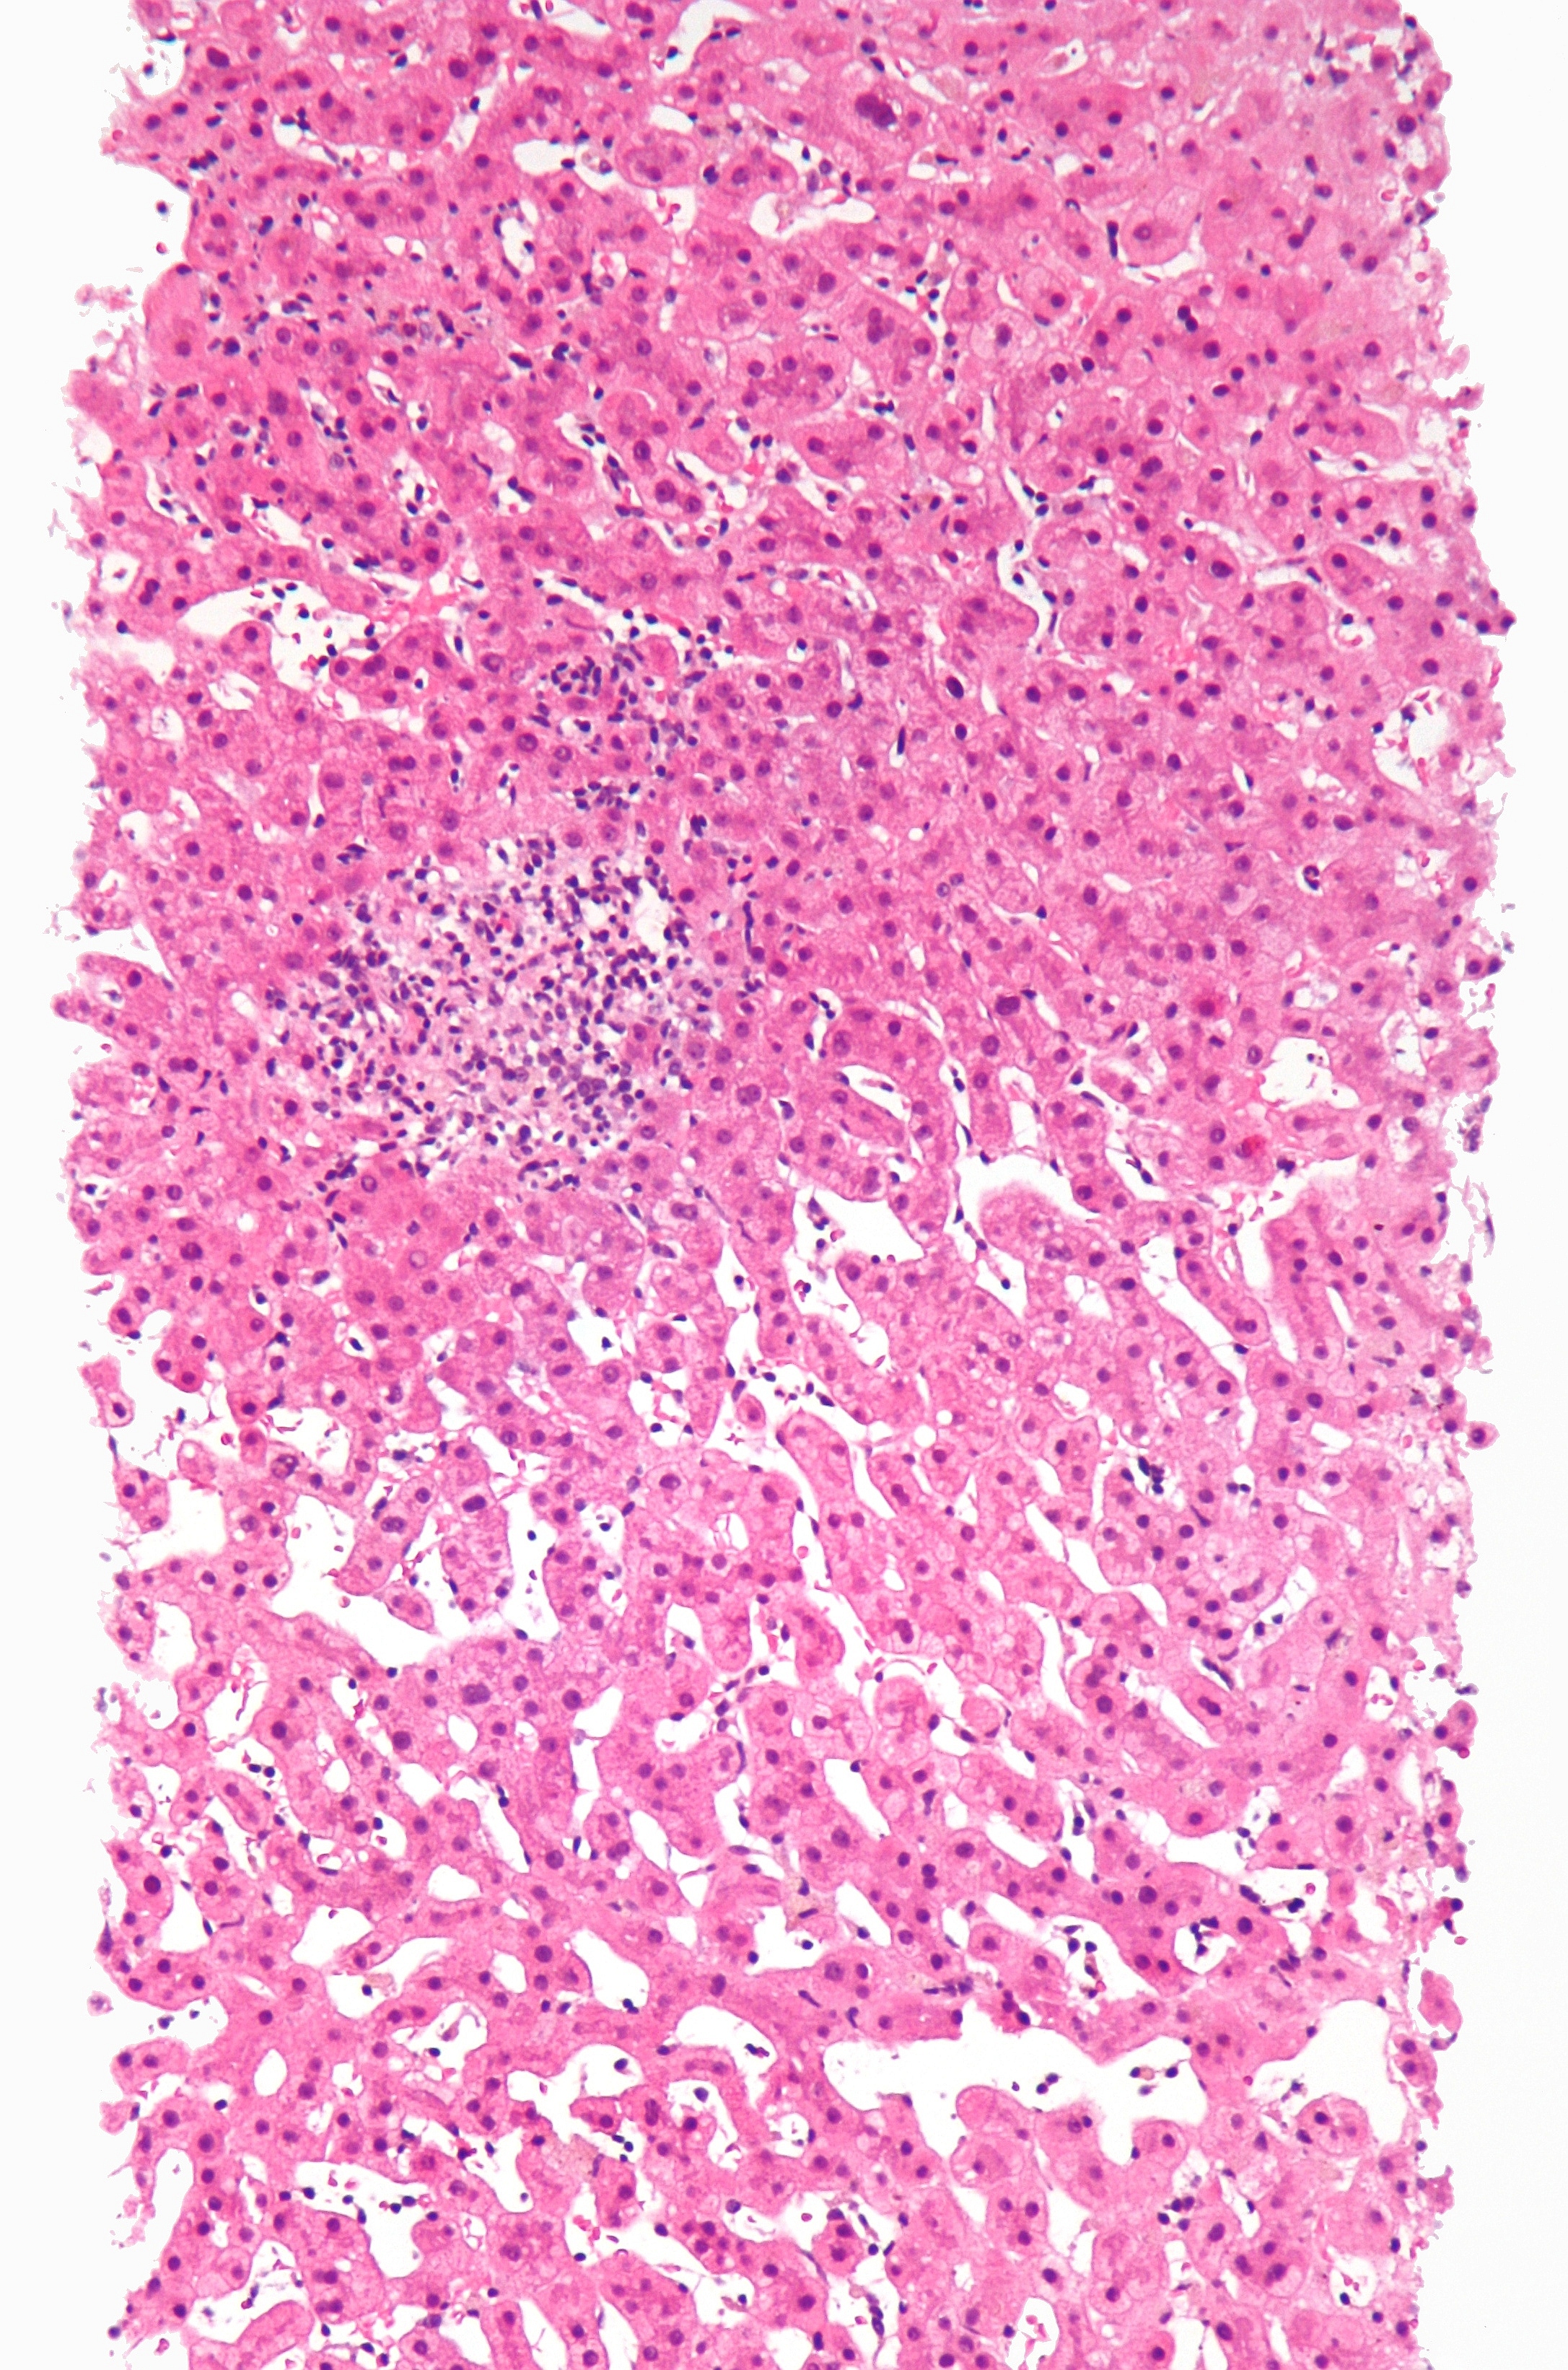

약물로 인한 간 손상의 구체적인 조직병리학적 양상은 다음과 같다.

'''구역 괴사''' (Zonal Necrosis)

약물 유발성 간 괴사 중 가장 흔한 형태이다. 손상이 주로 간 소엽의 특정 구역에 한정되어 나타난다. ALT 수치가 매우 높게 나타날 수 있으며, 심각한 간 기능 장애를 동반하여 급성 간부전으로 이어질 수 있다.

- 원인 약물: 파라세타몰(아세트아미노펜), 사염화탄소

'''간염''' (Hepatitis)

간세포 괴사와 함께 염증 세포의 침윤이 동반되는 양상이다. 약물 유발성 간염은 다음 세 가지 유형으로 나눌 수 있다.

- 바이러스성 간염형: 가장 흔하며, 조직학적 특징이 급성 바이러스성 간염과 유사하다.

- 원인 약물: 할로세인, 이소니아지드, 페니토인

- 국소성 또는 비특이성 간염: 산재된 세포 괴사 부위에 림프구 침윤이 동반될 수 있다.

- 원인 약물: 아스피린

- 만성 간염형: 임상적, 혈청학적, 조직학적으로 자가면역간염과 매우 유사하다.

- 원인 약물: 메틸도파, 디클로페낙